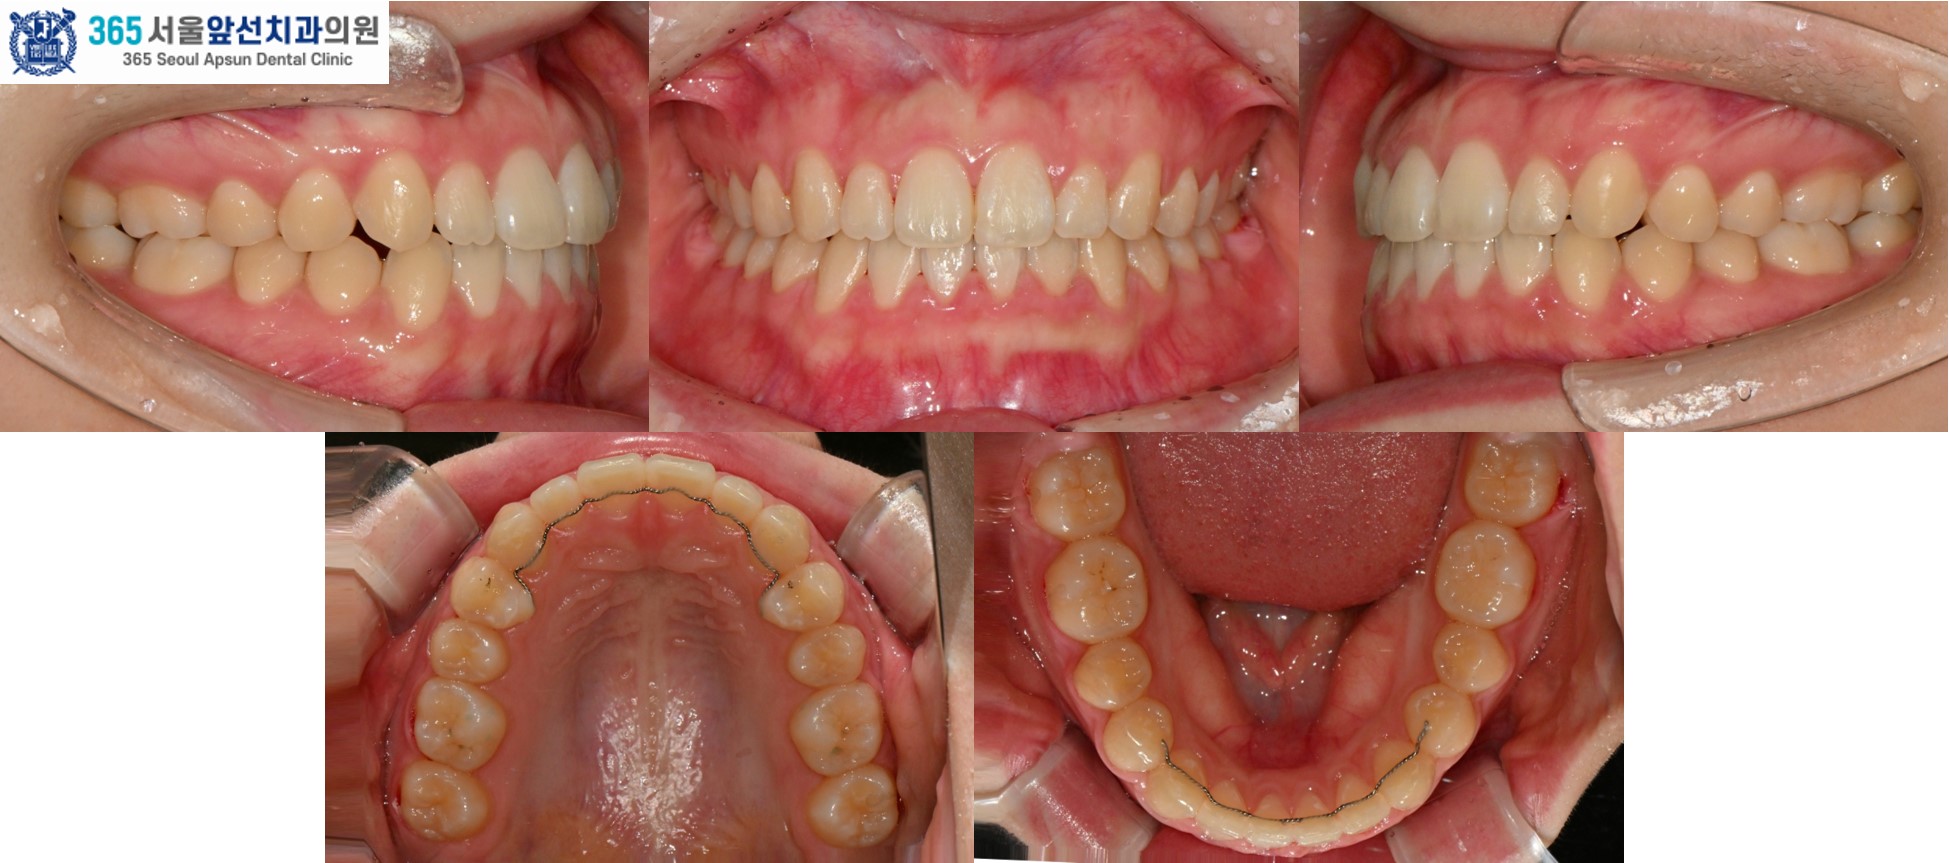

촬영일시 : 2024.10.23. / 2025.11.12. 반대로 물리는 이 때문에 입술이 비틀어져 보인다는 고민으로 내원하신, 성장이 완료된 10대 청소년 환자 분의 증례를 소개드리겠습니다.

촬영일시 : 2024.10.23. 치료 전, 우측 측절치와 견치(송곳니)의 반대교합과 정중선 불일치가 관찰됩니다. 양측 상악 측절치가 5.6mm 폭경으로 왜소치 경향을 보이며 Bolton 의 전치부 비율이 86.73으로, 이상적인 윗니와 아랫니 앞니의 비율을 고려한 폭경에 비해 5.0mm가 부족합니다. 이 경우, 왜소치의 폭경을 키워 수복한다면 이상적인 교합을 형성할 수 있습니다. 해당 환자분께서는 왜소치의 수복 없이 치료하기를 원하셔서, 보상적으로 하악 치열의 폭경 감소와 Canine key compromise를 통해 최대한 심미적이고 기능적인 교합을 만들어드렸습니다.